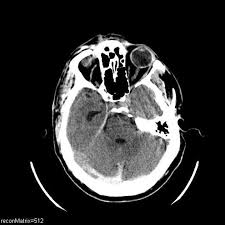

Unenhanced And Enhanced Axial Cts Of Brain Shows A Large Serpiginous Avm Adjacent To The Tentorium Radiology Imaging Radiology Interventional Radiology